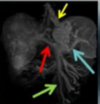

**_NOTE A DRENAGEM VENOSA_** **_1.VERDE = VEIAS MESENTÉRICAS SUPERIOR_** **_2.AZUL = ESPLENICA_** **_3 . VERMELHO = PORTA PRINCIPAL =_** **_4.AMARELO = ESSOFAGO_** **_CASO DE VARIZES ESOFÂGICAS_**